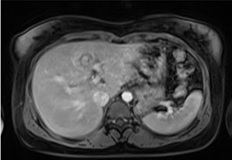

Hình 7: Tổn thương nằm sát nhánh trái tĩnh mạch cửa.

MRI: Gan ở hạ phân thùy IVb có tổn thương 26 x 27 mm, với viền mô đặc dày 6-7 mm ở ngoại vi bao quanh cấu trúc dạng dịch 11 mm. Phần mô đặc có tín hiệu thấp trên T1W, cao nhẹ trên T2W, bắt thuốc tương phản mạnh không đồng nhất. Tổn thương có vị trí nằm rất sát nhánh trái tĩnh mạch cửa. Tĩnh mạch cửa và các tĩnh mạch gan bình thường.

Chẩn đoán MRI: Tổn thương ở hạ phân thùy IVb gan trái, gợi ý thai ngoài tử cung.